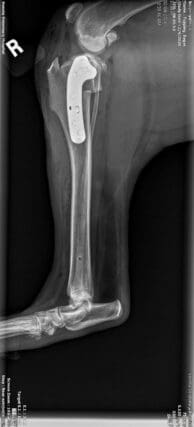

The puppy turned out to be a very sweet malinois mix, about 5 months old. He was limping but it was not a recent injury–he’d probably been hit by a car and left to shift for himself. Follow-up X-rays revealed a broken pelvis that had already started to heal. The vet recommended we keep him calm and build up his strength gradually. So Laura settled the pup, dubbed Gabe, into her own home.

Sadly, Gabe’s mobility has worsened rather than improved. He’s clearly in pain, and a second set of x-rays show that his pelvis has healed crookedly, impeding his mobility. At this point his hind leg is only in the way. Amputation is Gabe’s best option for a pain-free life. The surgery will cost at least $3,000 if it goes as planned.